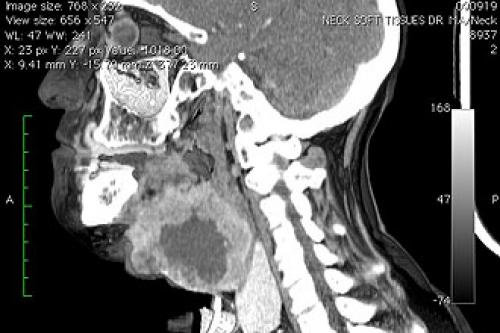

Давит в горле ниже кадыка, что делать. Боль в горле при шейном остеохондрозе: как диагностировать, чем лечить

Боль в горле при остеохондрозе шейного отдела позвоночника.

Казалось бы, нет никакой взаимосвязи между остеохондрозом шеи и болью в горле. Этот симптом характерен для большинства вирусных, бактериальных, грибковых респираторных инфекций — бронхитов, бронхиолитов, острых тонзиллитов. Но боль не исчезает после полоскания антисептическими растворами, рассасывания противовоспалительных пастилок, драже и леденцов. После проведения ряда инструментальных и лабораторных исследований устанавливают причину дискомфорта в горле и гортани. Это остеохондроз, обычно локализованный в шейном отделе позвоночника. Поэтому для устранения болезненных ощущений требуется лечение основной патологии опорно-двигательного аппарата. После ее переведения в стадию устойчивой ремиссии исчезнут першение,, проблемы с проглатыванием пищи.

Диагноз на рентгене.

Боль в горле при шейном остеохондрозе имеет нейровегетативное происхождение, связанное с близкой локализацией верхних дыхательных путей к шейным позвонкам. Остеохондроз — дегенеративно-дистрофическая патология, причина развития которой окончательно не установлена. В результате нарушения диффузного обмена начинают разрушаться хрящевые ткани дисков, дестабилизируя позвонки. Пытаясь сохранить функциональную активность позвоночника, организм запускает процесс формирования костных наростов () для удерживания позвонков в анатомически правильном положении. Острые края разросшихся костных пластинок сдавливают мышцы, кровеносные сосуды. Из-за разрушения дисков быстро сокращается расстояние между позвонками. При соприкосновении они защемляют чувствительные спинномозговые корешки, расположенные между этими костными структурами. Полноценная передача нервных импульсов становится невозможной. Если нервные окончания имеют общую иннервацию с респираторными структурами, то появляются боли в горле при остеохондрозе шейного отдела позвоночника.

При возникновении неприятных ощущений в горле рекомендуется в первую очередь обратиться за консультацией к терапевту. После осмотра пациента и изучения сопутствующих симптомов врач выпишет направление к узкопрофильному специалисту, в компетенции которого лечения кома в горле. В большинстве случае это может быть отоларинголог, эндокринолог, онколог, вертебролог, гастроэнтеролог и психотерапевт.

Из дополнительных исследований для выявления причин кома в горле целесообразно назначение лабораторных методов (общий анализ крови и биохимия), УЗИ щитовидки, МРТ или рентгена шейного отдела позвоночника. В таком случае решение принимает терапевт.